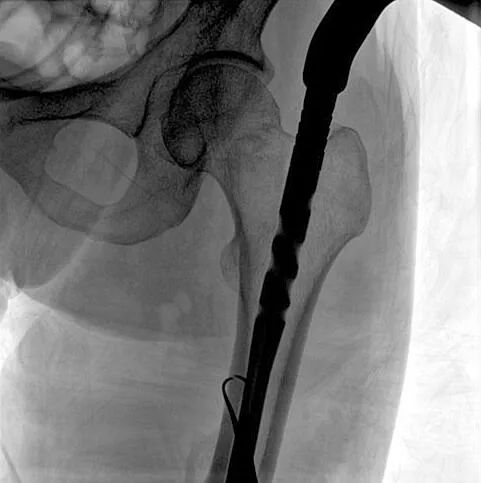

C形臂輔助手術(shù)過程

術(shù)中使用普愛醫(yī)療大平板一體式C形臂進(jìn)行透視,判斷骨折情況及克氏針、髓內(nèi)釘?shù)冉饘僦踩胛锏奈恢茫M(jìn)行調(diào)整。C形臂準(zhǔn)確的術(shù)中定位,大大縮短了手術(shù)的時(shí)間,減輕了患者的痛苦,輔助手術(shù)順利完成。

在進(jìn)行髓內(nèi)釘內(nèi)固定術(shù)時(shí),醫(yī)生需要同時(shí)觀察到入釘點(diǎn)和骨折部位的情況,普愛醫(yī)療大平板一體式C形臂采用30CM×30CM的平板探測器,能夠呈現(xiàn)更廣闊的成像面積,滿足大部分長骨髓內(nèi)釘內(nèi)固定術(shù)的攝片需求。